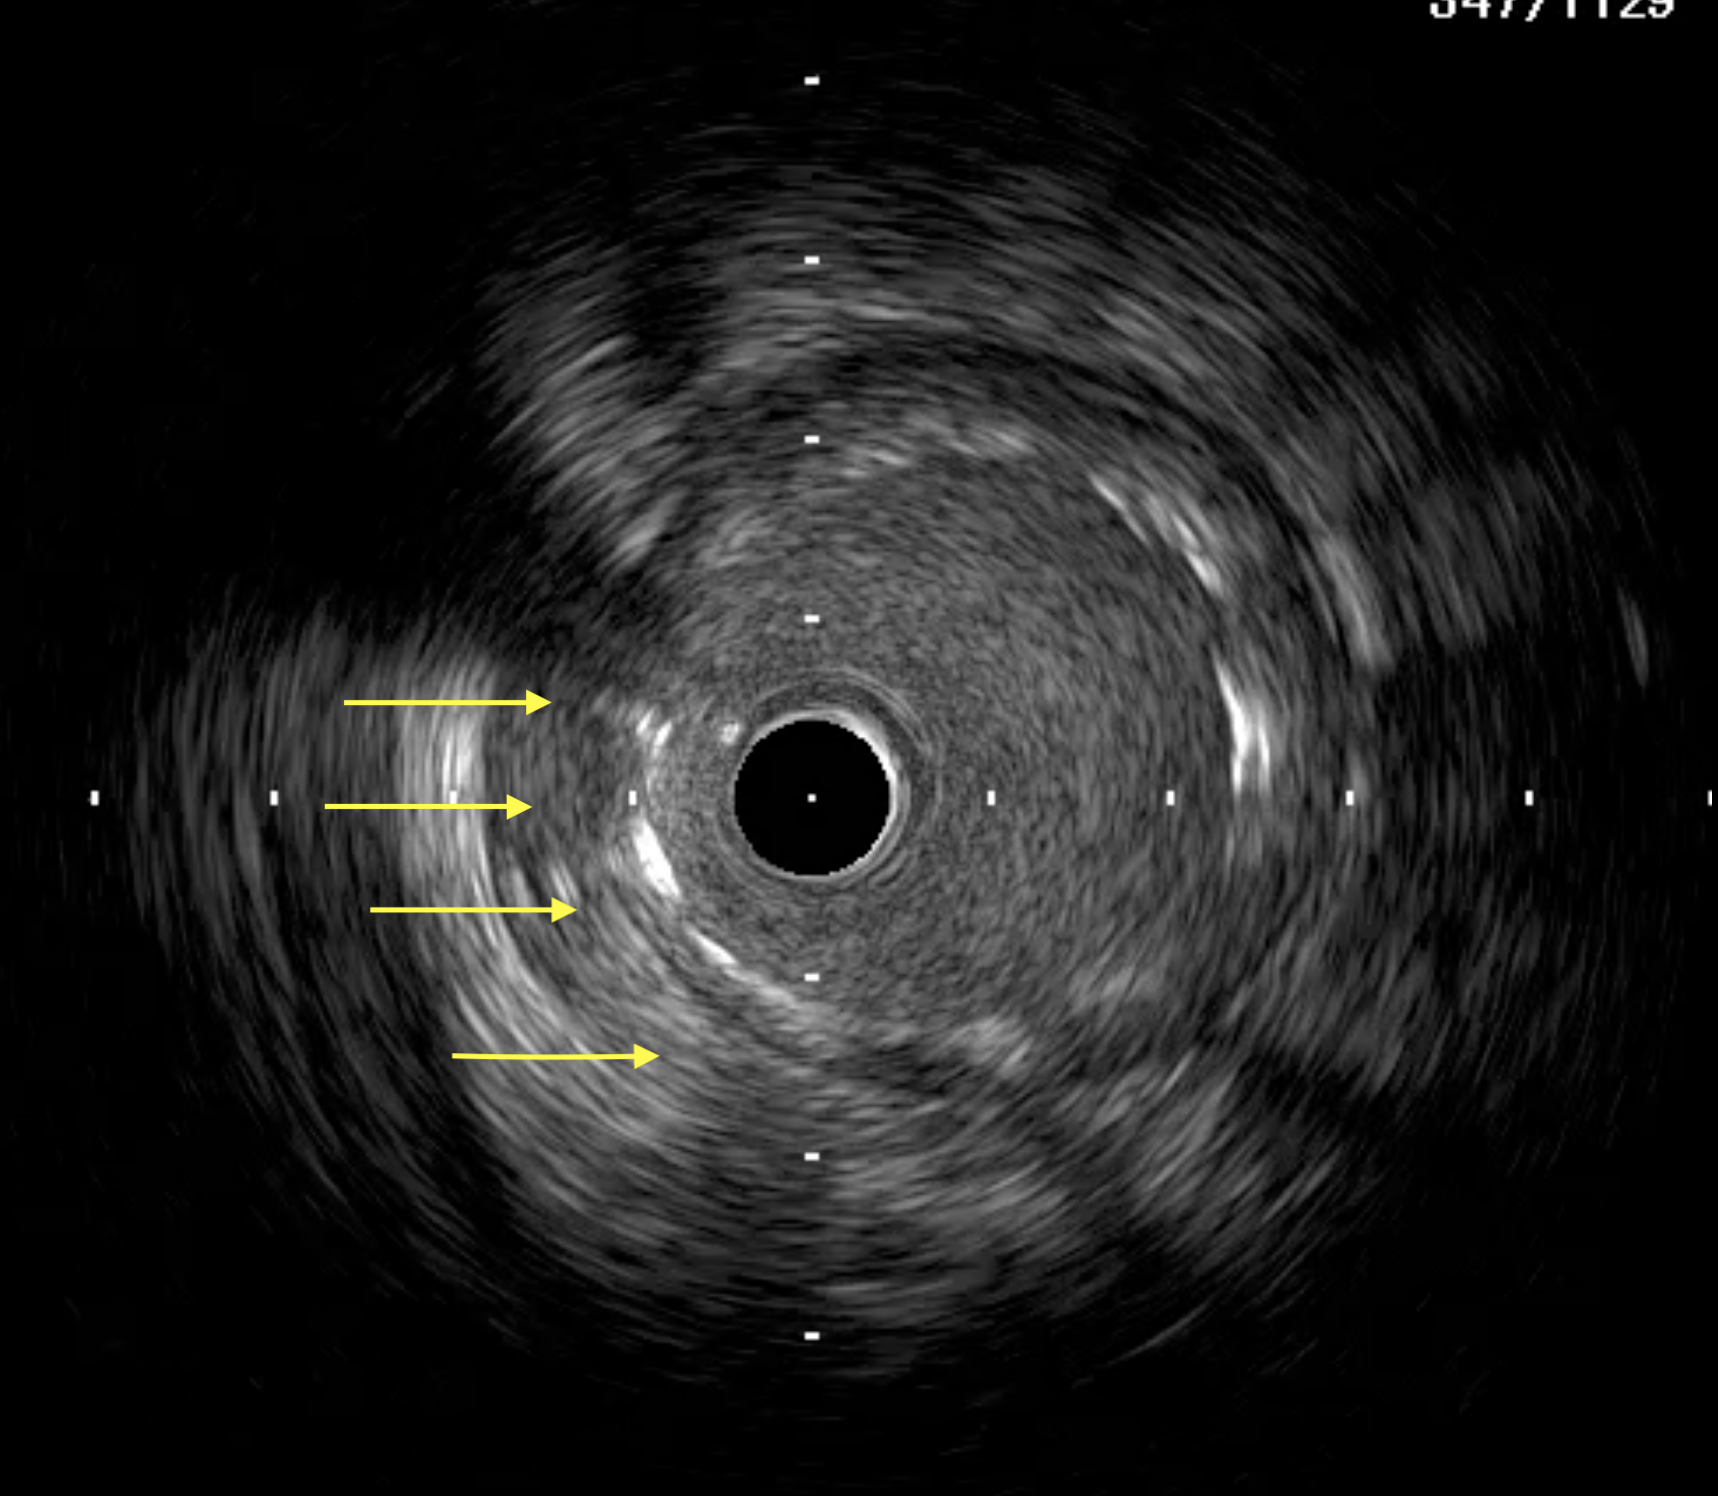

A 51-year-old man presented with stable angina and previously failed right coronary artery (RCA) CTO PCI. During RCA CTO PCI (Figure 1), the wire was inserted into the extraplaque space (Figure 2, Video 1). Intravascular ultrasound (IVUS) showed a hematoma (Figure 3A, Video 2). Live 3-dimensional tip detection IVUS wiring was successful (Figure 4, Video 3). A FineCross microcatheter (Terumo) was placed over the first wire into the extraplaque space and blood was withdrawn by connecting a negative indeflator to the microcatheter. Stents were deployed (Figure 5) and postdilated. Post-IVUS showed almost complete resolution of the hematoma (Figure 3B, C; Video 4) with good results (Figure 6, Video 5).